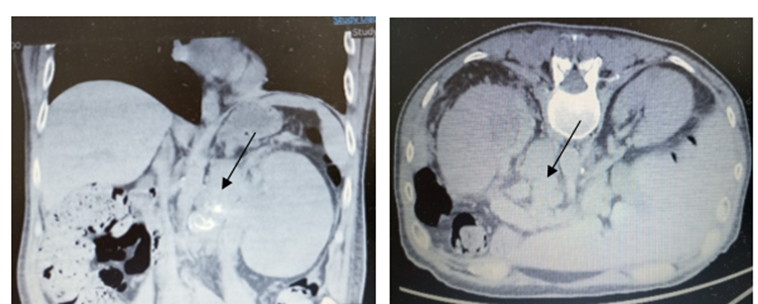

The patient was admitted under Urology care, and CT scan of thorax, abdomen and pelvis (Figure.2) was carried out.

Findings:

Thorax:

Correctly inspired pulmonary parenchyma, with mild emphysematous changes. Solid pulmonary nodule measuring 5 mm in size in the Right Lower Lobe (RLL). Left pleural effusion measuring 2 cm with associated compressive atelectasis. No mediastinal, hilar, or axillary adenopathy was observed.

Abdomen and pelvis:

Diffuse hepatic steatosis, with a 2.5 cm hypervascular lesion in segment IVA and another measuring 11 mm in segment III. Pancreas, right adrenal gland, and RK are unremarkable. Extensive hypodense mass occupying the LK and the proximal portion of the ureter, with signs of invasion of the ipsilateral RV. Left paraaortic mass left measuring 7,7 x 6,5 cm that could correspond with extension of tumour mass versus adenopathic conglomerate. Nodules in left perirenal area with size up to 22 mm suggestive of tumorous implants. Left suprarenal thickening with a nodule measuring 17 mm suggestive of secondary affection. Bladder and prostate without significant alterations. No suspicious characteristic bone lesions. Upper left urothelial neoplasm, locally advanced with signs of left RV invasion, and an extensive left paraaortic adenopathic conglomerate. Left suprarenal thickening with a nodule suggesting metastasis. Focal hypervascular, nonspecific hepatic lesions, to be evaluated by MRI. Solid pulmonary nodule measuring 5 mm in size in the RLL, to be evaluated on follow-ups. Left pleural effusion.

Figure 2: Enlarged LK with areas of hypocaptation of the renal parenchyma, suggestive of areas of necrosis (black arrows).Extensive hypodense mass occupying the LK and the proximal portion of the ureter, with signs of invasion of the ipsilateral RV (yelow arrow). Left paraaortic mass left measuring 7,7 x 6,5 cm (blue arrow). Nodules in left perirenal area suggestive of tumorous implants (white arrow).